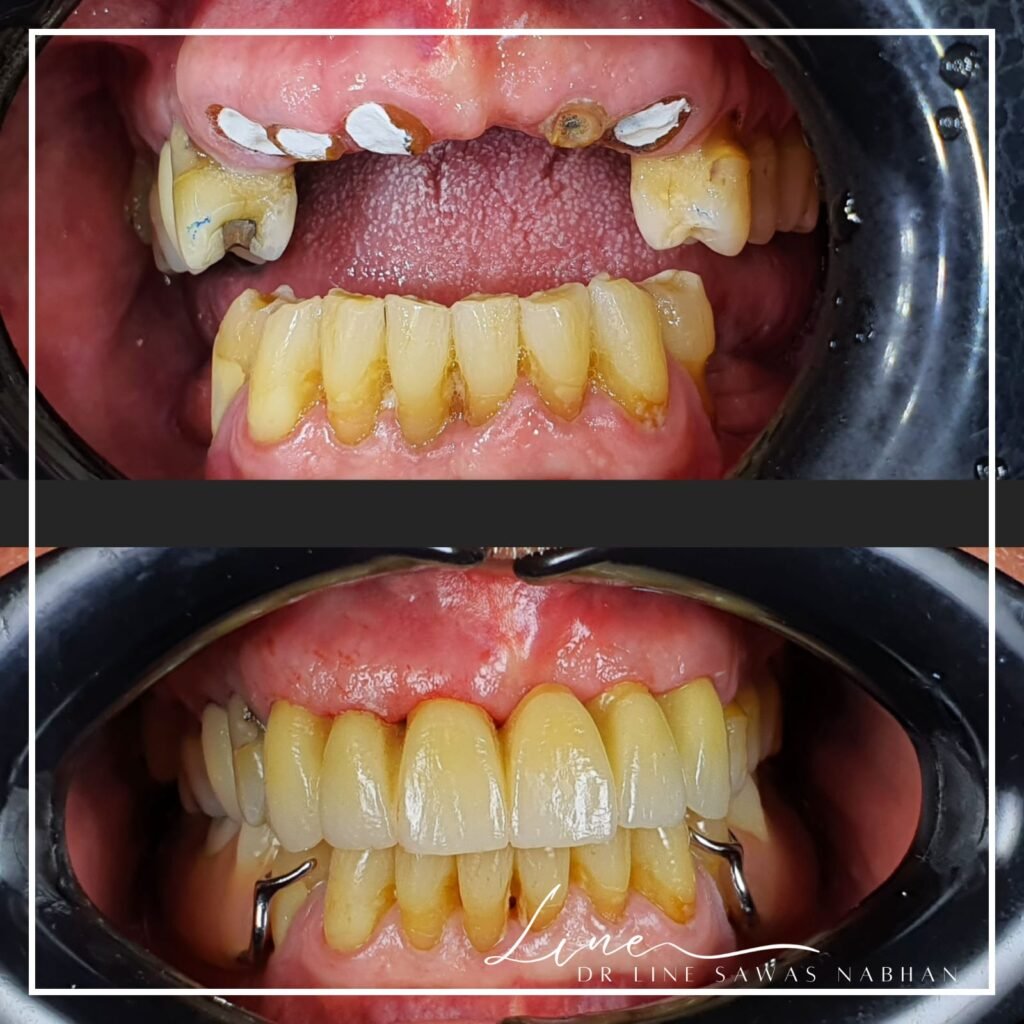

Avant et après

Couronnes dentaires

: Résultat avant/après facettes dentaires à Agdal, Rabat par dentiste

Avant et après facettes dentaires par dentiste à Agdal, Rabat

Transformation avec facettes dentaires par dentiste à Agdal Rabat

Avant et après traitement de facettes dentaires à Agdal Rabat